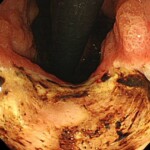

*痛み止めによって発生した胃潰瘍

④胃以外の病気によるもの